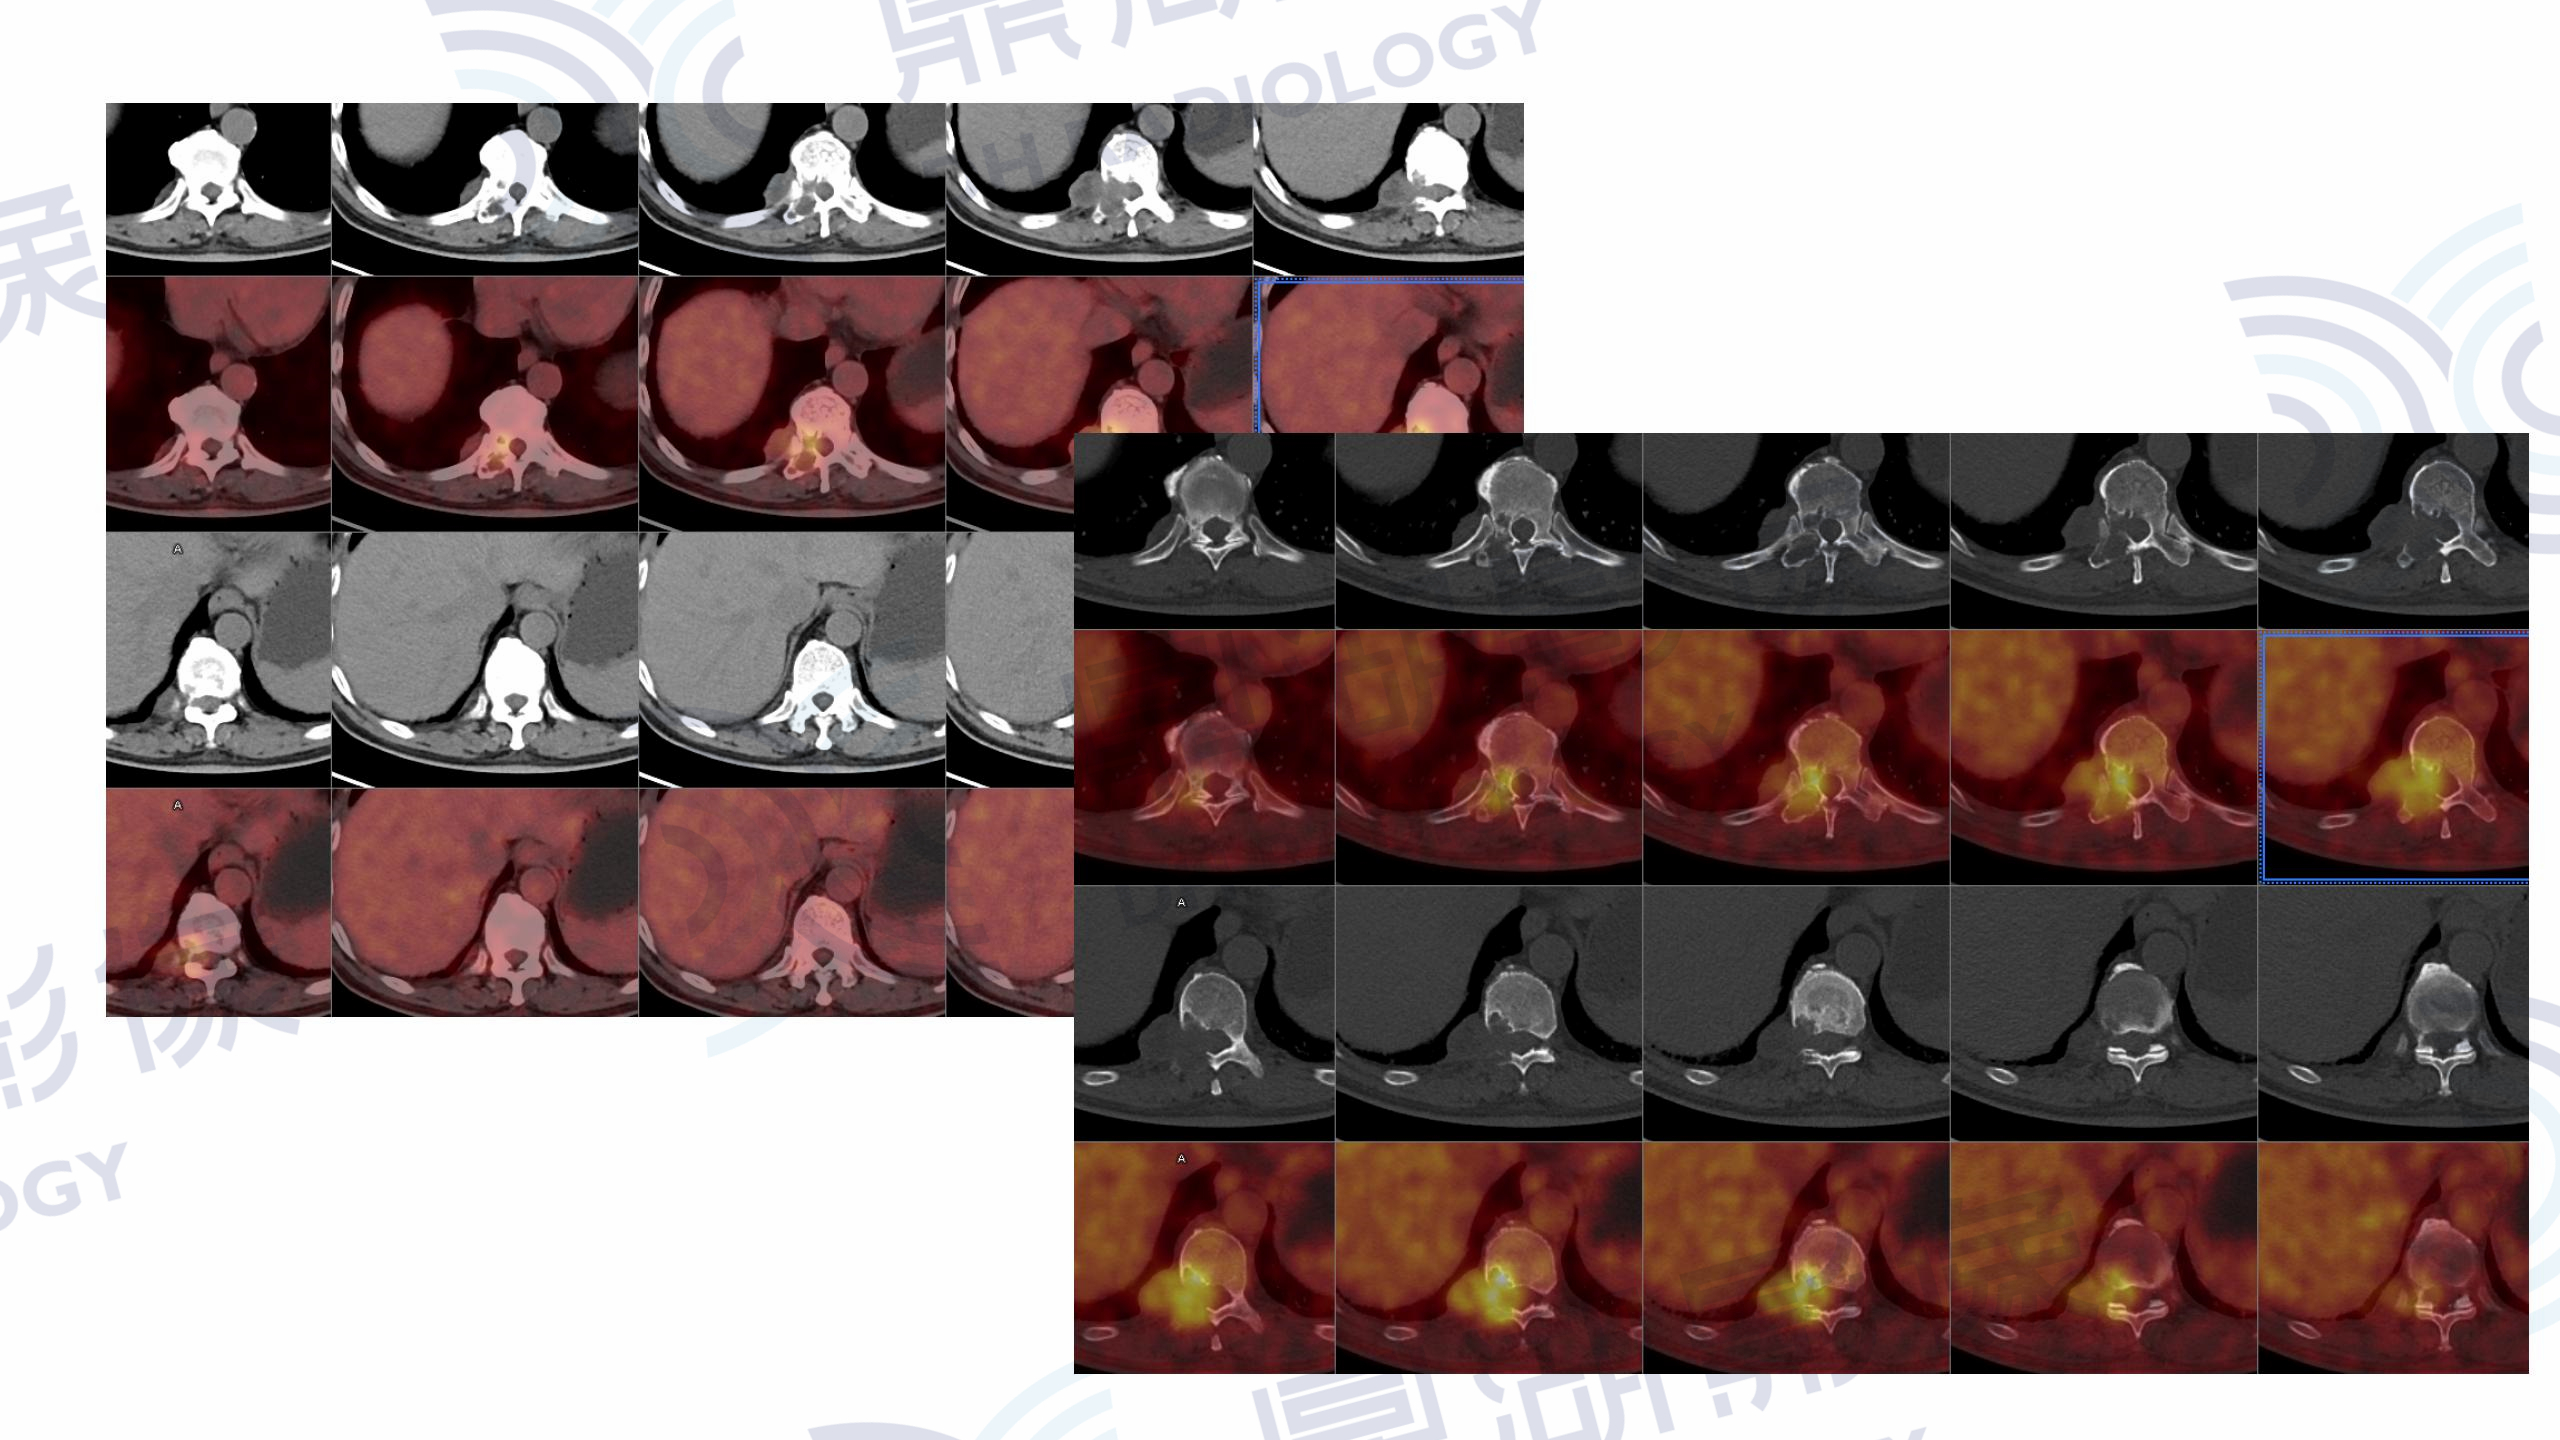

男性 73岁发现胸椎占位1周。体检时发现胸椎占位,进一步MR示T10水平椎管右侧占位,当地考虑神经源性肿瘤。

本中心PET/CT检查提示:胸10右侧椎体、椎弓及横突明显溶骨性骨质破坏伴软组织肿块,病灶跨右侧椎间孔生长,

可见低密度囊变,肿块范围约42mm×28mm,局部压迫脊髓,SUVmax=6.3。